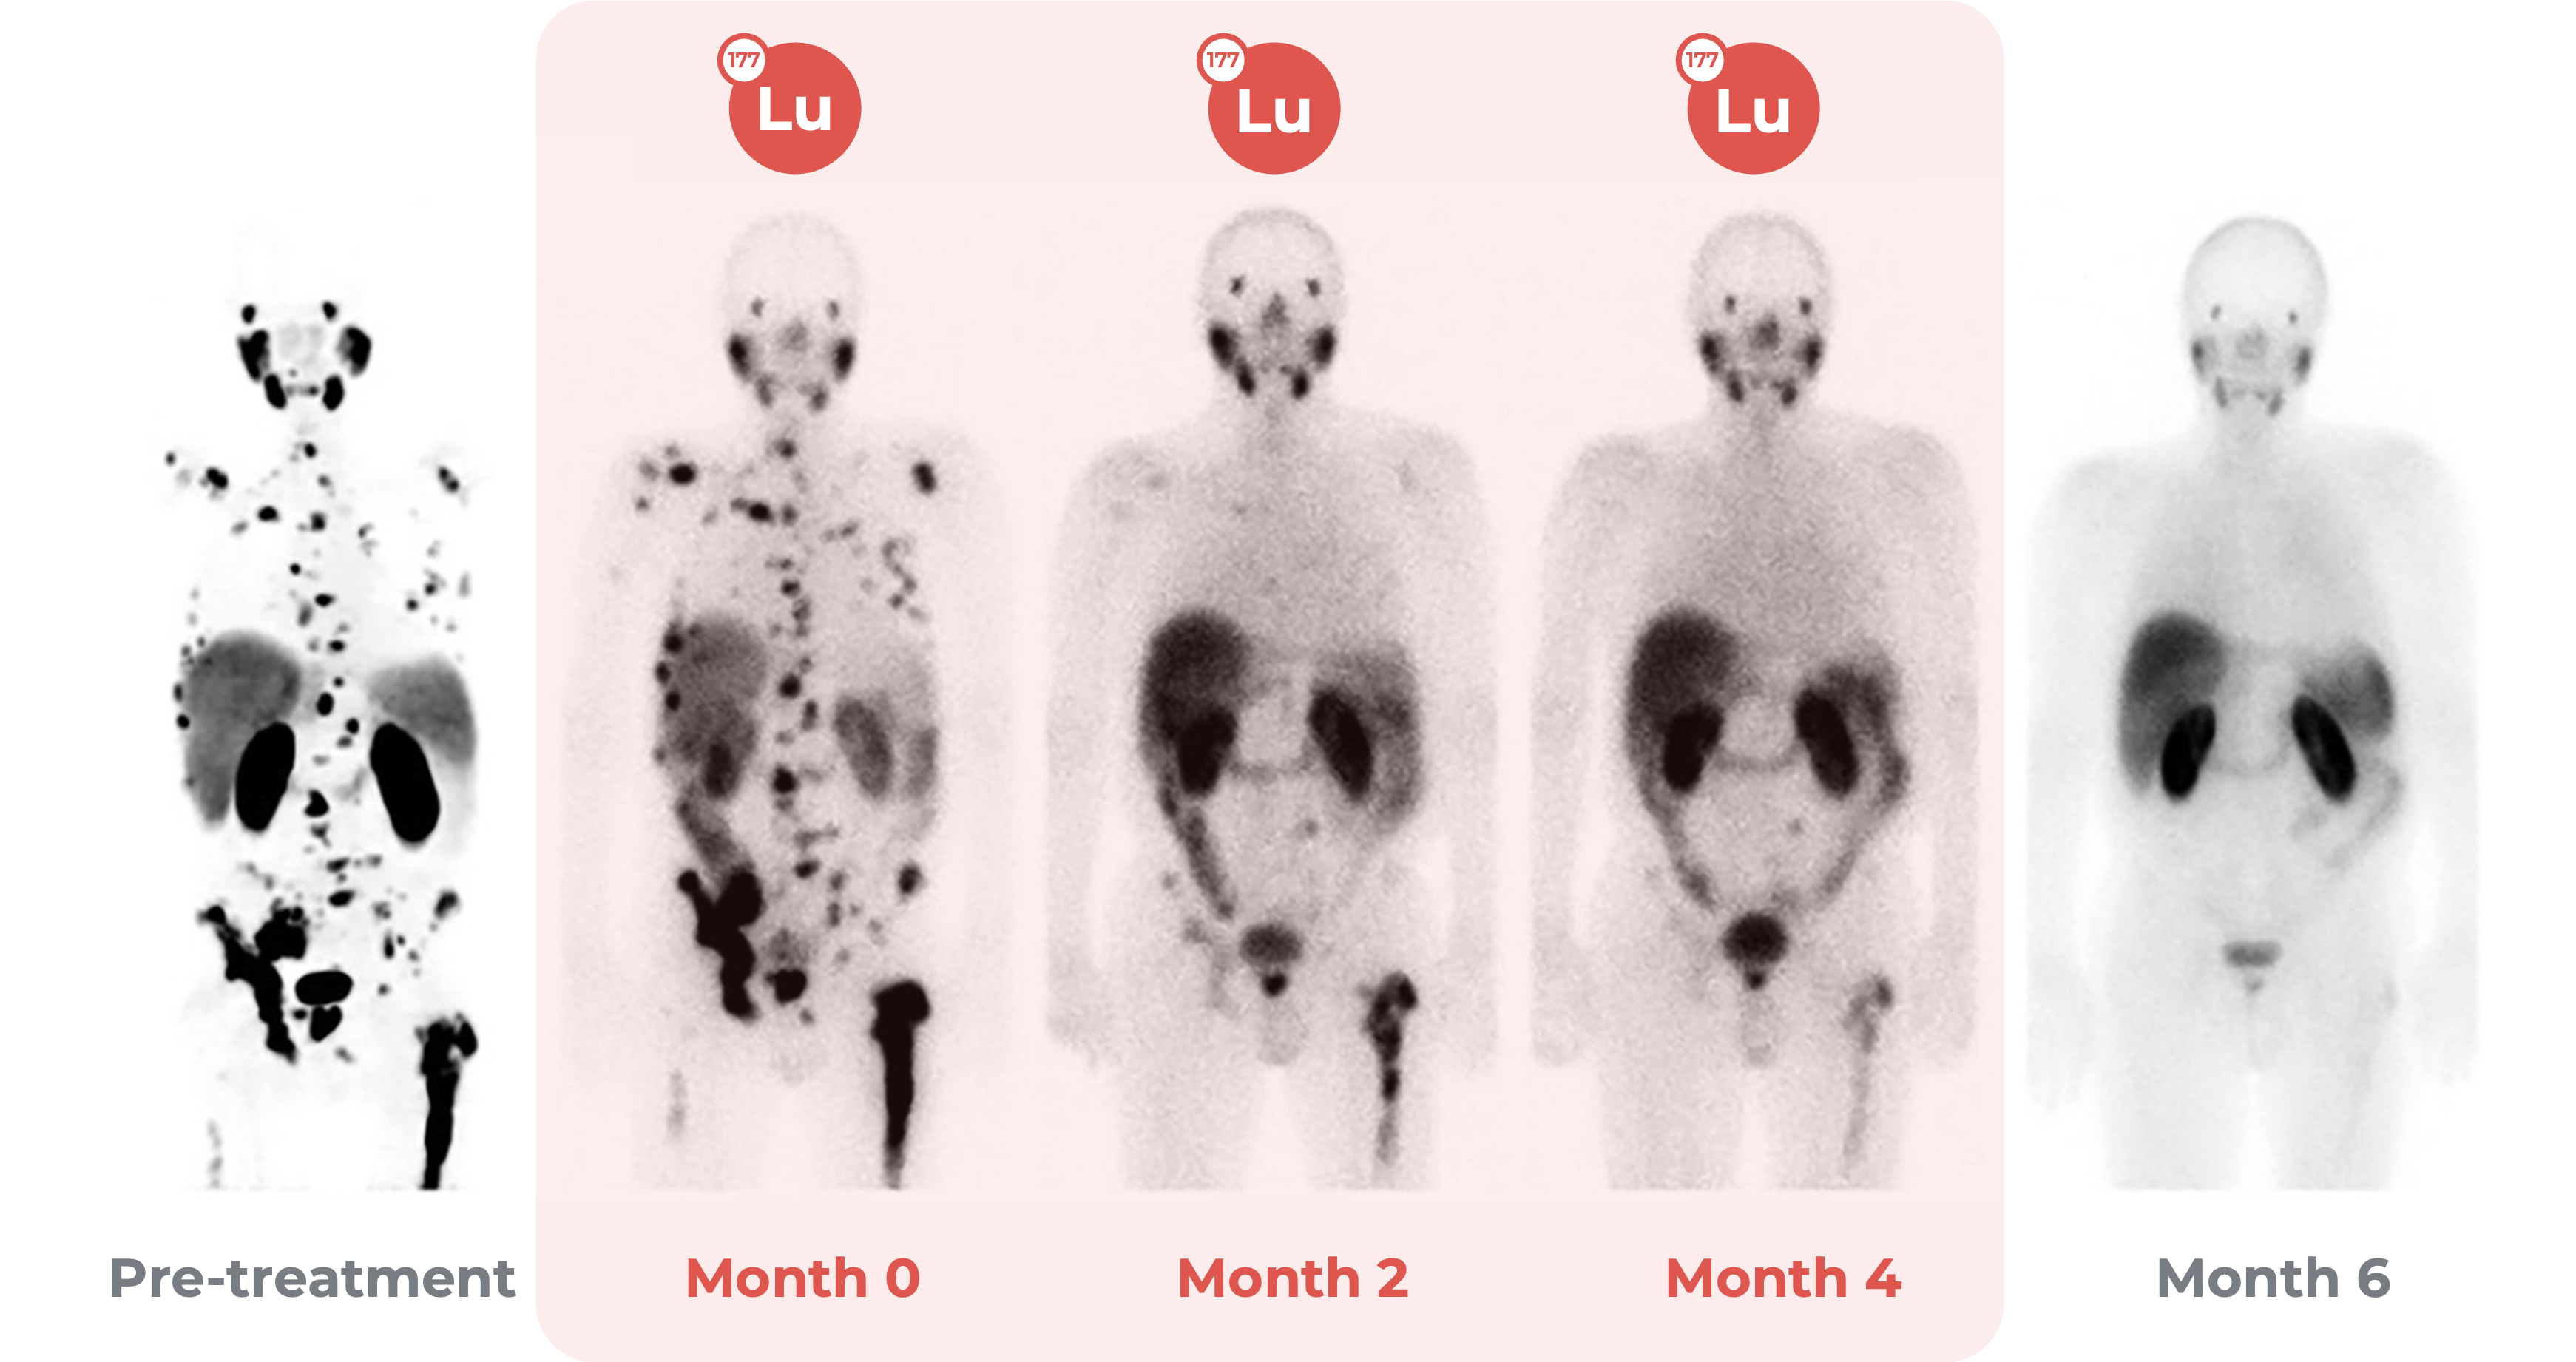

This image shows a prostate cancer patient. The spots in the Pre-treatment image are cancerous growths.

To treat this patient’s cancer a radioisotope-based pharmaceutical was administered.

Multiple rounds of treatment (Month 0-4) produced a successful effect. The cancer no longer appeared on image scans by month six. (Image adapted from source)

Source PDF: Hun Yee Tan, Chai Hong Yeong, Yin How Wong, Molly McKenzie, Azahari Kasbollah, Mohamad Nazri Md. Shah, Alan Christopher Perkins, Neutron-activated theranostic radionuclides for nuclear medicine, Nuclear Medicine and Biology, Volumes 90–91, 2020, Pages 55-68, ISSN 0969-8051, Link.